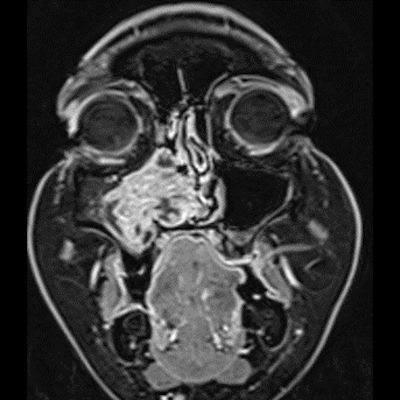

- A) Koronal T2 ağırlıklı görüntülerde sol maksiller sinüs lümenini dolduran, belirgin ‘convoluted’ (karmaşık-kıvrımlı) serebriform patern sergileyen lezyon (oklar), kontrastlı seride heterojen ve yoğun kontrastlanma göstermektedir (oklar). Perfüzyon incelemesinde pedinkülünde perfüzyon artışı gösterdiği, diğer kontrastlanan segmentlerin nispeten hipoperfüze olduğu görülmektedir (ok).

- MR incelemesinde sinonazal inverted papilloma tipik olarak T2 ve post-kontrast T1 serilerde ‘convoluted’ serebriform paternde heterojen sinyal ve kontrastlanma gösteren, pedinküler orijininde daha belirgin perfüzyon artışı sergileyen, genellikle difüzyon kısıtlaması izlenmeyen ve komşu sinüs duvarlarında ekspansiyona bağlı remodelinge yol açabilen benign ancak lokal agresif karakterde bir yumuşak doku kitlesi olarak izlenir.